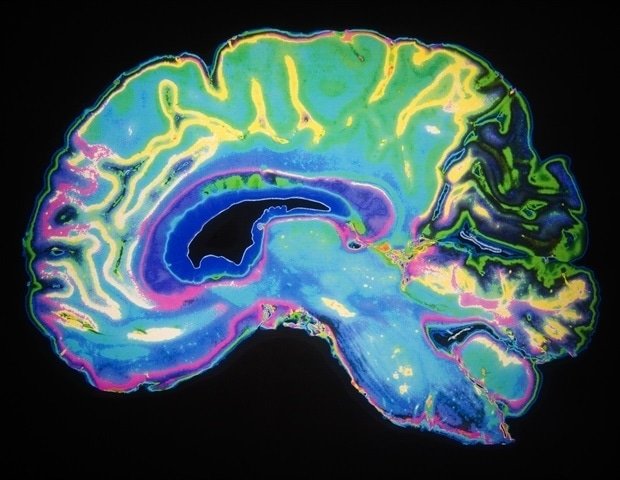

Tanycytes are a type of non-neural brain cell that resides primarily in the third ventricle of the brain. Previous studies have shown that these cells play an active role in exchanging metabolic signals between blood and cerebrospinal fluid (CSF), the fluid that surrounds the brain and spinal cord and acts as a communication hub to maintain homeostasis.